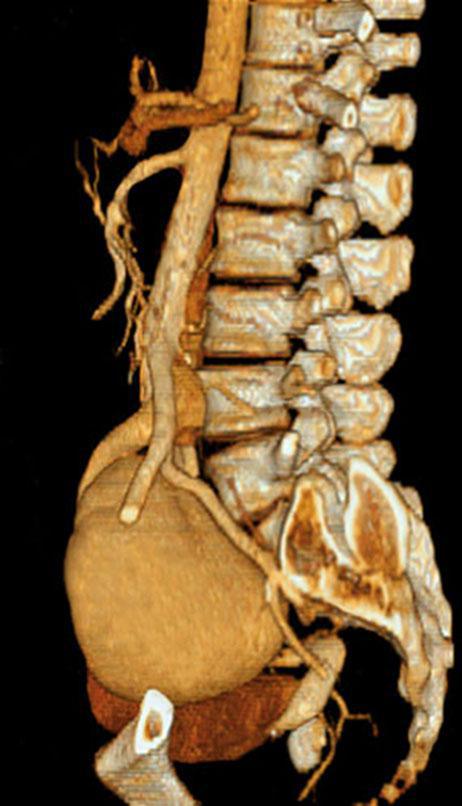

Riñón único pélvico